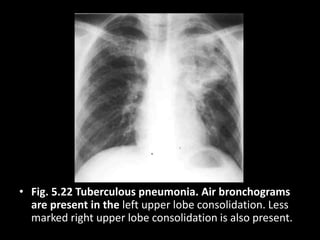

• Fig. 5.22 Tuberculous pneumonia. Air bronchograms

are present in the left upper lobe consolidation. Less

marked right upper lobe consolidation is also present.

• Fig. 5.22Tuberculous pneumonia. Air bronchograms are present in the left upper lobe consolidation. Less marked right upper lobe consolidation is also present.